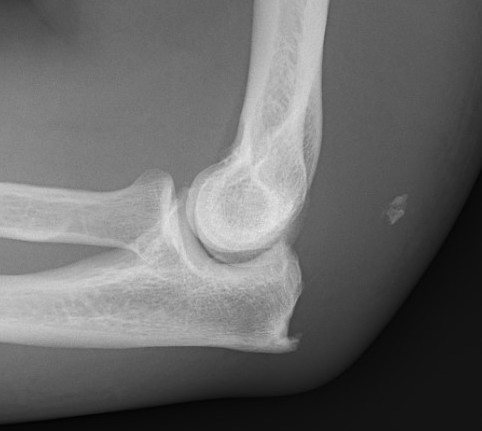

Xray

Olecranon avulsion